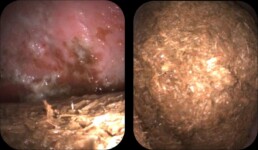

Weiterführende Untersuchungen: Endoskopie

- verminderte Magenentleerung trotz 12h Nahrungskarenz

- erneute Gastroskopie nach insgesamt 24h Hungerphase

- weiterhin Futterball im Magen vorhanden

- Magenschleimhaut nur teilweise beurteilbar

- hochgradige Magengeschwüre in Drüsenschleimhaut sichtbar